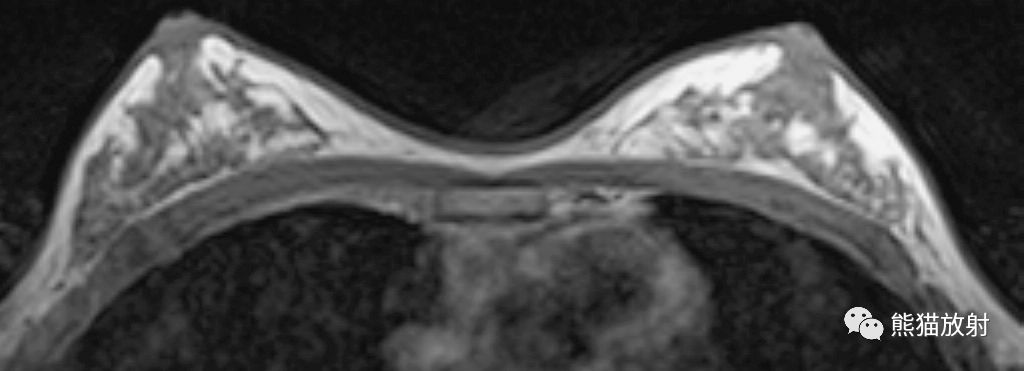

MR 轴位T1WI

1、乳头,2、输乳管及乳腺导管,3、皮肤,4、脂肪岛,5、Cooper's韧带,6、静脉,7、皮下脂肪,8、腺体,9、胸大肌,10、右肺,11、胸骨,12、心脏,13、前锯肌。